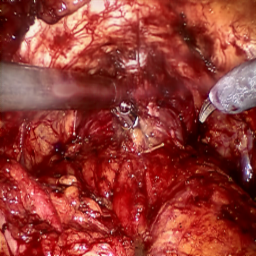

Refer to caption (a) Input Refer to caption (b) case1 Refer to caption (c) case2 Refer to caption (d) case3 Refer to caption (e) Ours Refer to caption (f) Target

Figure 4: Ablation comparisons sampled from the DesmokeData and LSD3K datasets. The first two rows are from DesmokeData and the last two rows are from LSD3K. (settings: case1 = ADA+CrossGating, case2 = DHA+CrossGating, case3 = DHA+ADA).

IV-D Ablation Studies

To validate the effectiveness and individual contributions of the core components of our proposed RGA-Net, we conducted a series of ablation experiments on the DesmokeData dataset. We systematically analyzed the impact of our key designs: the DHA module, the ADA module, and the Cross-Gating (CG) mechanism for feature fusion. In these studies, we created several variants of our network by removing or replacing one component at a time and evaluated their performance. The quantitative results of these experiments are presented in Table II, and qualitative visual comparisons are shown in Fig. 4.

IV-D1 Effectiveness of the Dual-Stream Hybrid Attention Module

The DHA module is designed to capture both local surgical details and global illumination changes by combining shifted window attention with a frequency-domain processing branch. To ablate its effect, we replaced the DHA modules in the encoder with standard Swin Transformer blocks, thus removing the spectral pathway and the hybrid attention mechanism. As demonstrated in Table II, this variant experienced a significant drop in performance. This decline highlights the importance of integrating frequency-domain information, which is crucial for handling the complex light scattering caused by surgical smoke and restoring high-frequency textural details. The results confirm that the dual-stream approach provides a richer feature representation than spatial attention alone.

IV-D2 Effectiveness of the Axis-Decomposed Attention Module

We then investigated the contribution of the ADA module, which is employed in the decoder and latent space to efficiently process multi-scale features. We created a variant where the ADA modules were substituted with a more conventional self-attention mechanism without the block and grid axis decomposition. The results in Table II show a clear degradation in performance for this variant compared to the full model. This outcome validates that factorizing attention along two distinct axes allows the model to capture both fine-grained local patterns and long-range spatial dependencies more effectively and efficiently. The ADA module’s design provides a powerful yet computationally manageable way to model complex feature relationships during the reconstruction phase.

IV-D3 Effectiveness of the Cross-Gating Mechanism

Finally, we analyzed the efficacy of the cross-gating mechanism used for multi-scale feature fusion between the encoder and decoder. We replaced our CG blocks with a standard skip-connection method, specifically simple concatenation followed by a convolutional layer, as is common in many U-Net-based architectures. As shown in Table II, this change resulted in a substantial performance decrease. This finding underscores the superiority of the bidirectional feature modulation offered by our CG mechanism. Unlike simple fusion, cross-gating allows the encoder and decoder pathways to selectively amplify relevant features and suppress irrelevant information from each other, leading to a more refined and effective integration of multi-scale context, which is vital for high-quality image reconstruction.

In conclusion, the ablation studies comprehensively demonstrate that each of our proposed components—DHA, ADA, and CG—is integral to the overall performance of RGA-Net. The full model consistently outperforms all ablated variants, proving the synergistic benefits of our architectural design for the challenging task of surgical smoke removal.